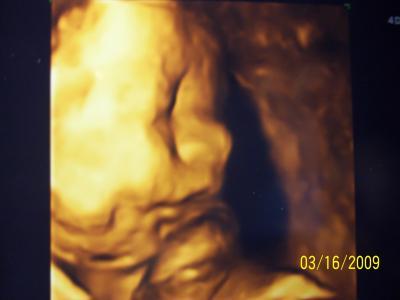

Hallo Mädels, komme gerade von meinem letzten Ultraschall, ich wurde von der 29ssw auf die 31ssw korrigert, anhand der Messungen des Babys: ca. 1,6 Kg und ca 40 cm lang, auweia so langsam wird es ernst. Er muss sich auch noch drehen, er liegt noch mit dem Kopf nach oben...

Bild zu Juhuu, letzter Ultraschall gemacht. - Forum für August - Mamis

Warum steht denn auf dem Bild 16.03.2009?

Ach, die Kamera wurde nie richtig eingestellt, darauf darf man nicht achten. Mein Sohn darf nicht faul sein, er muss sich bald drehen. Mein ET wurde ebenfalls nicht korrigiert, naja kommen eh nur 5% aller Babys genau am berechneten ET-Tag

Schön dass alles ok ist! Und das Foto ist ja goldig sieht richtig propper aus dein Kleiner. Ja und zum Drehen - keine Sorge, er wird sich schon noch drehen!! GLG